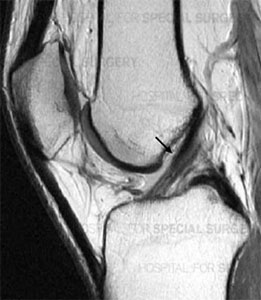

ACL - badanie lekarskiePodczas pierwszej wizyty badamy specyficzne objawy i zbieramy wywiad dotyczący urazów. Podczas badania fizykalnego sprawdzane są wszystkie struktury kontuzjowanego kolana i porównywane do zdrowych struktur w drugim kolanie. Właściwie większość urazów więzadła może zostać zdiagnozowana w drodze gruntownego badania lekarskiego.

Badania obrazowe mogą jednak pomóc w potwierdzeniu diagnozy po badaniu fizykalnym, bądź uwidocznić współistniejące uszkodzenia innych struktur:

- Badanie rentgenowskie (RTG): Choć to badanie nie uwidoczni uszkodzenia ACL, może jednak wykazać, czy uraz jest powiązany ze złamaniem (np. złamanie Segonda bardzo często towarzyszące uszkodzeniu ACL) lub np. niestabilnością tylną jak w uszkodzonym Więzadle Krzyżowym Tylnym PCL (Posterior Cruciate Ligament).

ACL - badanie lekarskie USG

- Rezonans magnetyczny (MRI): Badanie to najdokładniej obrazuje tkanki miękkie, do których należy też Więzadło Krzyżowe Przednie. Rezonans magnetyczny nie jest jednak konieczny do rozpoznania przerwania lub niewydolności ACL.

- USG - badanie ultrasonograficzne stawu kolanowego dobrze uwidacznia większość struktur wewnątrz- i okołostawowych. Umożliwia także przeprowadzenie badania w ruchu (dynamiczne USG) i tu przeważa badanie rezonansem magnetycznym (MRI).